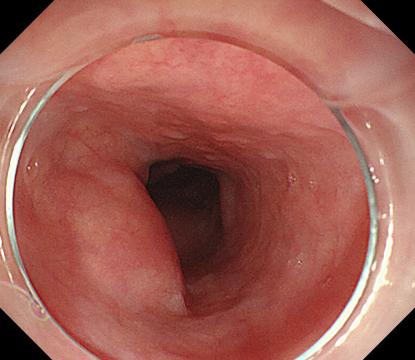

胃底間質瘤 內鏡下全層切除術后創面 切除后標本

內鏡下全層切除術(EFTR):治療消化道黏膜下腫瘤(最主要):起源于固有肌層深層、部分腔外生長、與漿膜層密不可分;少部分抬舉征陰性消化道癌前病變和早期癌;少部分困難解剖部位結腸病變(如結腸憩室內腺瘤)等。